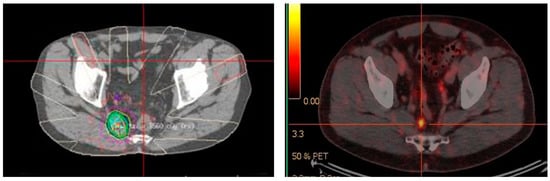

The high sensitivity of 68Ga-PSMA PET/CT, coupled with the increased expression in higher grade tumors, guided intra-prostatic biopsy has shown in several small studies that 68Ga-PSMA avidity correlates well with gross tumor volume as detected by multiparametric MRI and voxel based determinants directly matched to histopathological specimens [81,82]. This correlation supports the concept of utilizing these data to potentially reduce sampling error and improve diagnostic accuracy of targeted biopsy. Current prostatic biopsy is often performed blind, although MRI directed biopsy based on Prostate Imaging Reporting and Data System (PI-RADS) is being increasingly utilized [83,84,85,86]. The addition of 68Ga-PSMA PET/MRI may further improve the utility and accuracy of this technique and direct biopsy to the most relevant area within the prostate. This is exquisitely demonstrated in Figure 3.

Figure 3.

Primary prostate cancer. PIRADS 4/5 left lobe of prostate on multiparametric MRI. Fused to 68Ga-PSMA PET/CT images for MRI in-bore guided targeted biopsy.